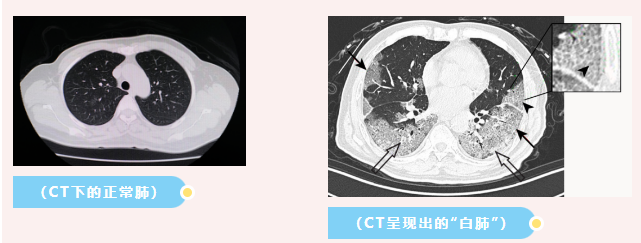

医生表示,“白肺”一般是指重症肺炎在X线或CT检查下的表现,患者肺部呈现一大片的白色状态,往往会出现呼吸困难、呼吸衰竭,严重者还会出现其他脏器功能障碍。

感染、弥漫性肺泡出血综合征等是“白肺”最常见的病因,除此之外,吸入有害物质如粉尘、喷雾等也可能会导致肺部出现大范围白色样病变,也就是说如果长期不正确使用防晒喷雾,有可能导致“白肺”。

据人民日报微博4月8日消息,前不久,湖南长沙一医院,一患者因呼吸困难和咳嗽前来就诊,CT影像显示双肺出现严重“白肺”。医生仔细询问后诊断,患者因对着面部喷涂防晒喷雾且有吸入情况,引起了急性过敏性肺炎。